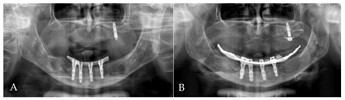

Orthopantomogram (OPG): (A) 4 months after first surgery—the prosthetic restoration’s finalization; (B) 24 months after bar-retained overdenture delivery.